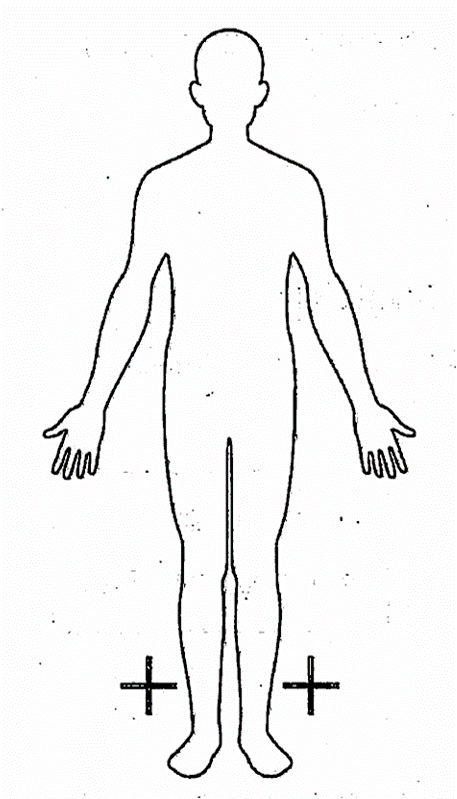

脳性麻痺患者における麻痺のある部位を「+」で表す模式図を示す。麻痺の部位による分類はどれか。1つ選べ。

a.片麻痺

b.単麻痺

c.対麻痺

d.両麻痺

解答を見る

c